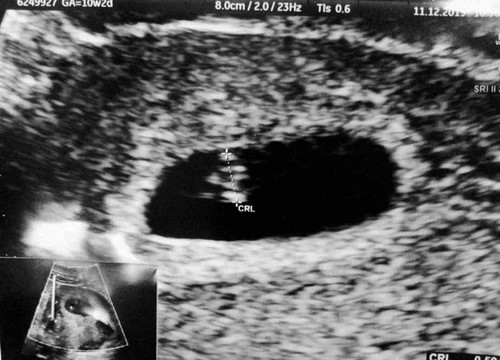

อัลตราซาวด์

6 สัปดาห์ 3 วัน ขนาดตัวอ่อน 0.56cm ถือว่าปกติไหมค่ะ